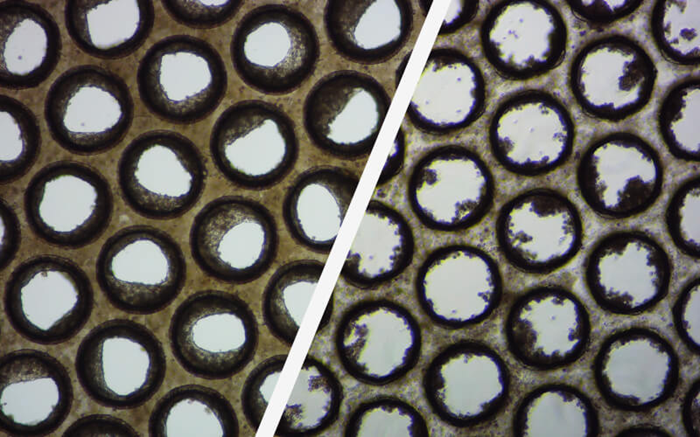

Image Credit: CN-Bio

These brightfield pictures show how the pores of individual Multi-chip Liver-12 plate scaffolds form good (left) and poor (right) liver microtissue formation.